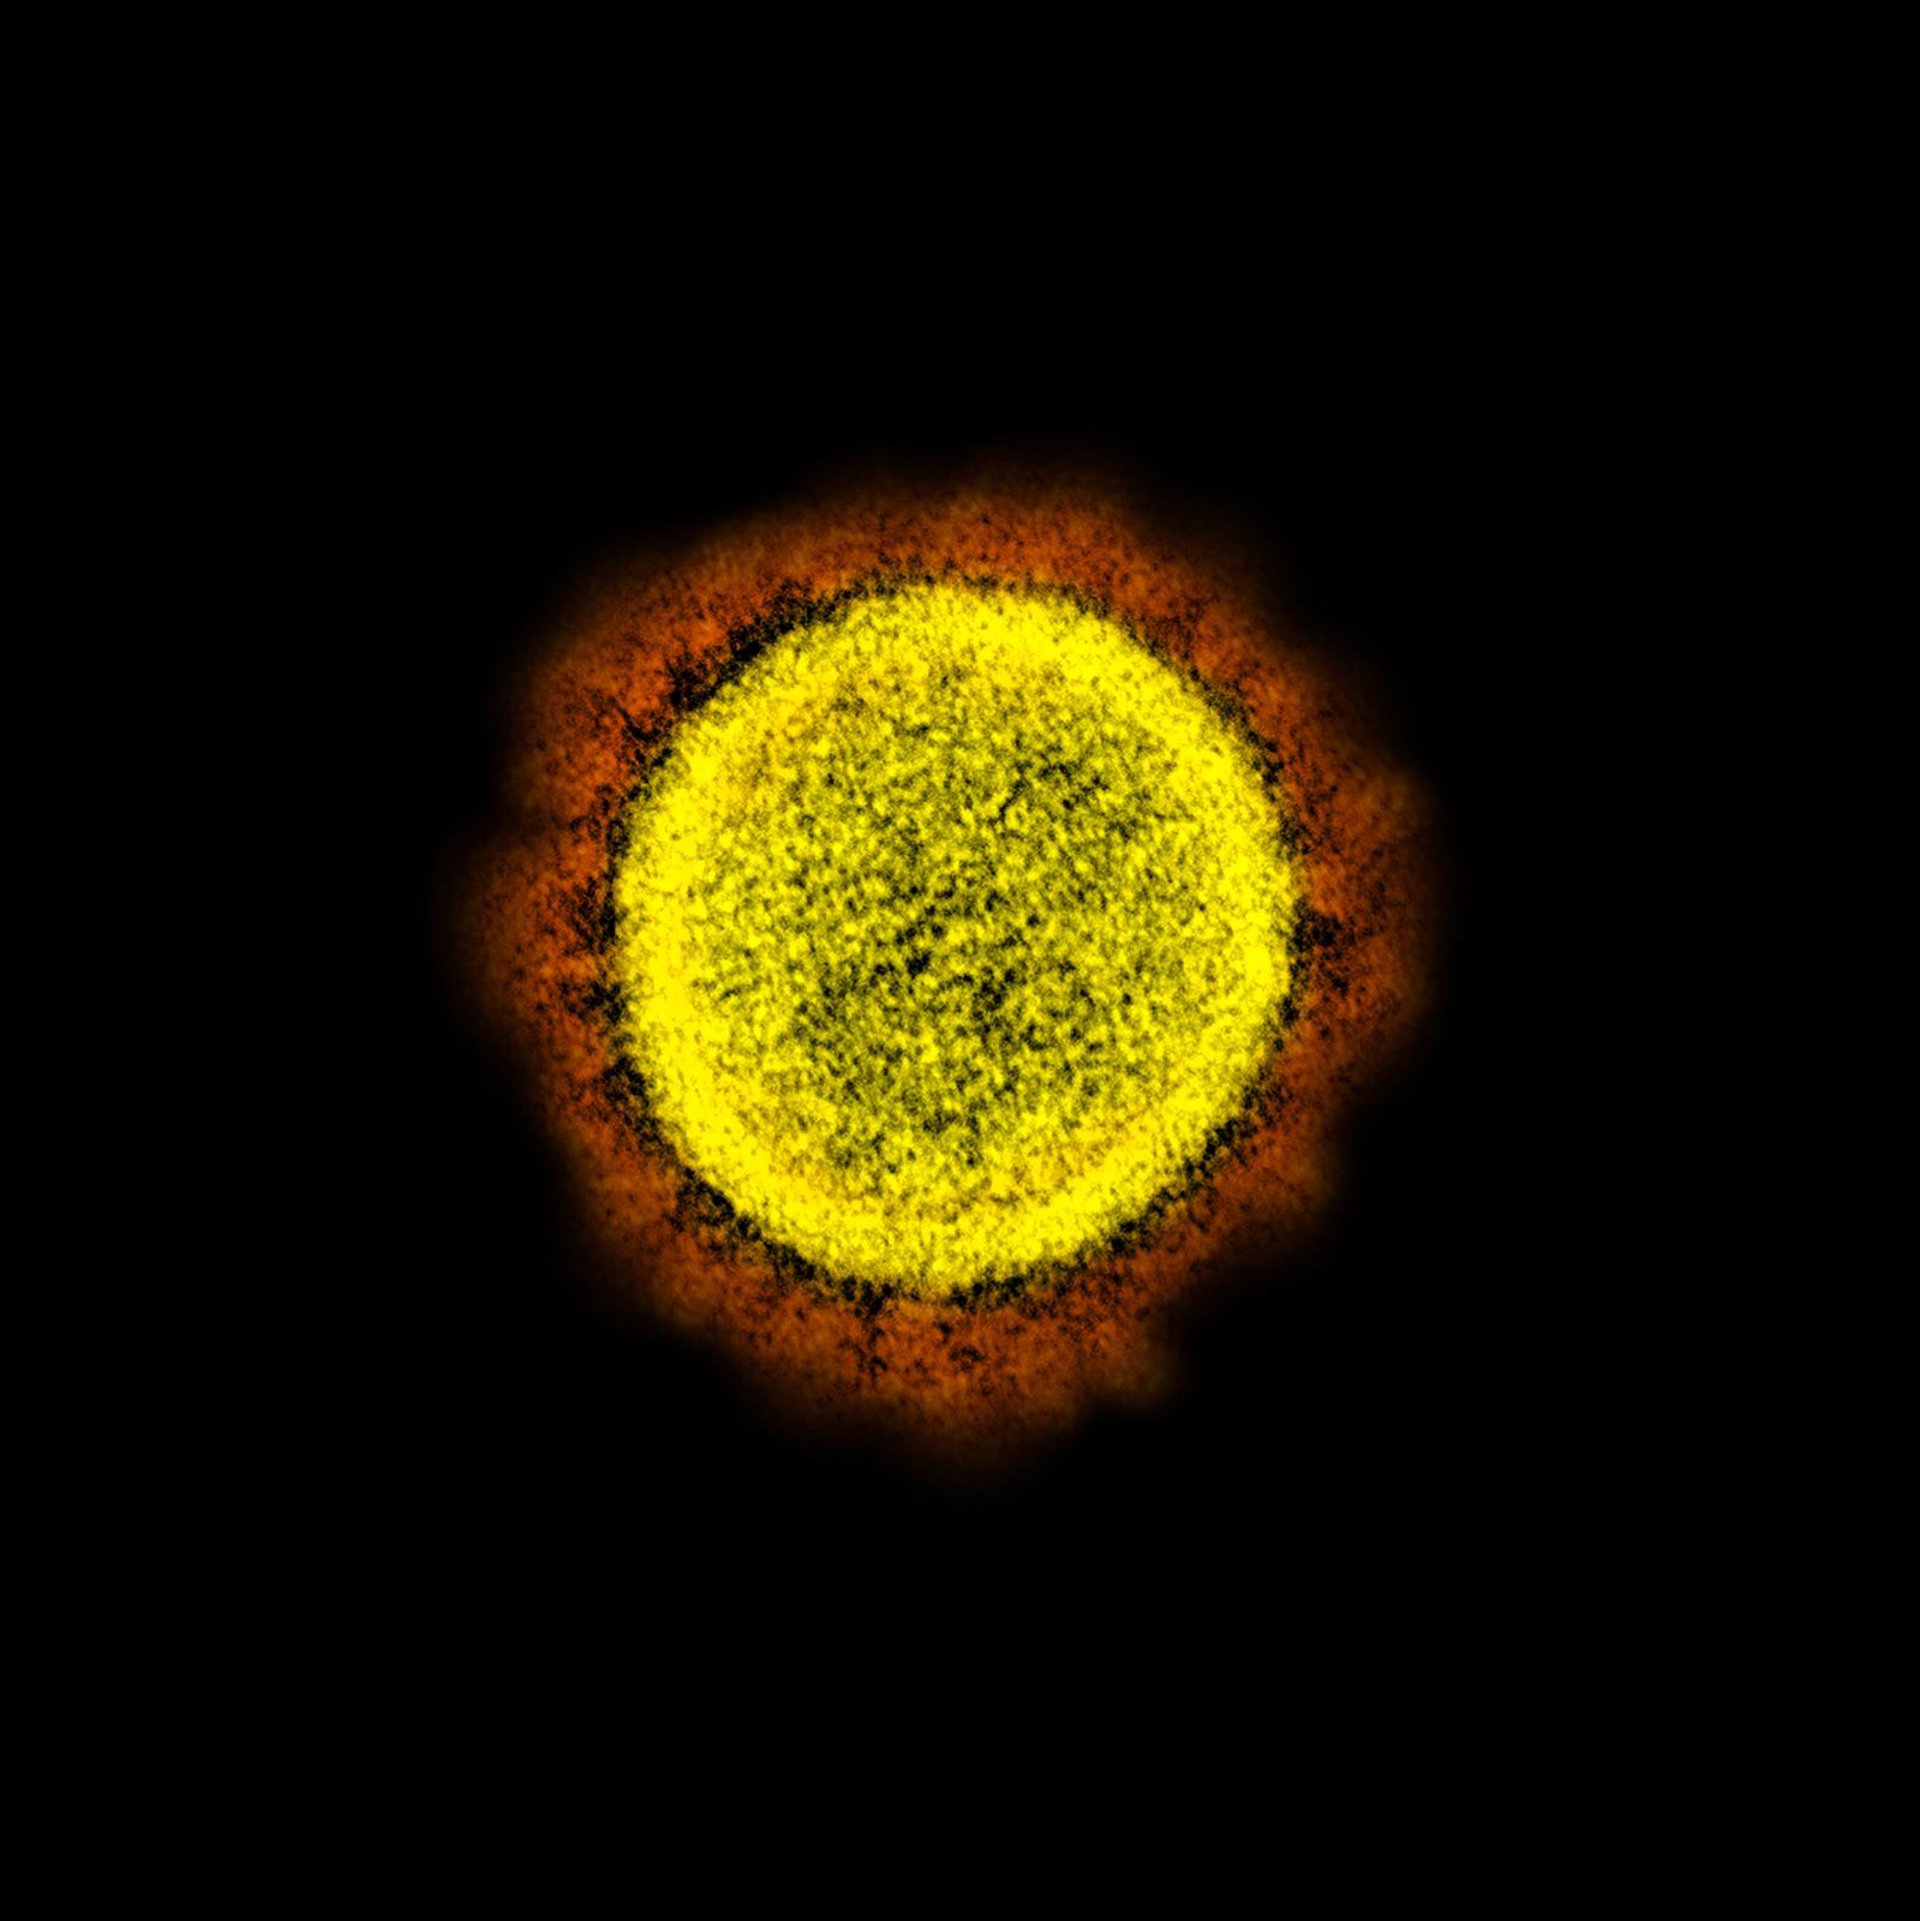

Micrografía electrónica de transmisión de partículas del virus SARS-CoV-2, aislada de un paciente, del Instituto estadounidense de Alergia y Enfermedades Infecciosas (NIAID) y con realce del color del Centro de Investigación Integrado, en Hamilton.

Micrografía electrónica de transmisión de partículas del virus SARS-CoV-2, aislada de un paciente, del Instituto estadounidense de Alergia y Enfermedades Infecciosas (NIAID) y con realce del color del Centro de Investigación Integrado, en Hamilton. - NIAID - Archivo